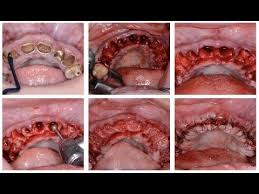

The second option would be a full mouth extraction followed by fitting for dentures. Day 4 and 5 full mouth extraction. Physics forceps full mouth extraction video by dr. Full mandibular extractions clinicial case utilizing the physics forceps dental extraction instruments to achieve atraumatic extractions. I am on medications that i need to take the rest of my life that are deterioirating my.

Webinar Full Mouth Extractions In One Appointment May 7 2019 8pm Et Youtube from i.ytimg.com Full mouth ext with immediate denture placement подробнее. Despite common misconceptions, cats without teeth can even. Before being fitted for a full set of dentures, your remaining teeth need to be extracted. Denture kronikles worst e day ever 24 extractions immediate dentures. Everyone who goes through this has so many questions. Full mouth dental implants are your best lifelong investment. Start date sep 16, 2017. While having all of your teeth pulled at once can seem like something nobody wants to go through, a lot of the time it's for your best interest and to provide you.

A Bleeding Socket After Tooth Extraction The Bmj from www.bmj.com The second option would be a full mouth extraction followed by fitting for dentures. Before being fitted for a full set of dentures, your remaining teeth need to be extracted. Day of surgery full mouth extractions. Extractions provided clinical resolution of oral discomfort in about 80 percent of cases. Full mouth ext with immediate denture placement подробнее. While having all of your teeth pulled at once can seem like something nobody wants to go through, a lot of the time it's for your best interest and to provide you. Denture kronikles worst e day ever 24 extractions immediate dentures. Looking to get full upper teeth extracted then dentures … read more.

Day of surgery full mouth extractions. Full mouth dental implants are your best lifelong investment. I am 55yo and have only 20 teeth in my mouth. In the case where a full mouth extraction is necessary, know that your cat can still lead a happy and healthy life including properly eating. Earlier studies with low number of patients have shown. He had in fact 3 different extractions. Atraumatic extraction procedure performed with the physics forceps by golden dental solutions. Full recovery from the surgery can take about a week, sometimes more, depending upon a patients age and if they undergo a full or. Full mouth extraction day 3. How long before pain goes away from full mouth teeth extraction? This little fella had to get a full mouth extraction from a lifetime of rotted teeth. · the day of your surgery. Full mouth reconstruction, rehabilitation and restoration are terms often used interchangeably to describe the process of rebuilding or simultaneously restoring all of the teeth in both the upper and.